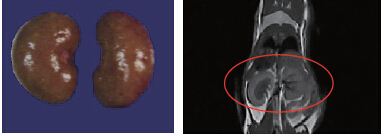

小鼠肿瘤直径3.8mm;打入新型Mn螯合造影剂0.5h之后,通过灰度平均值计算,发现肝脏与肿瘤造影明显。

44.8g小鼠,肾脏体积:0.315cm3,解剖体积(水溢法):0.293cm3,成像时间:10min